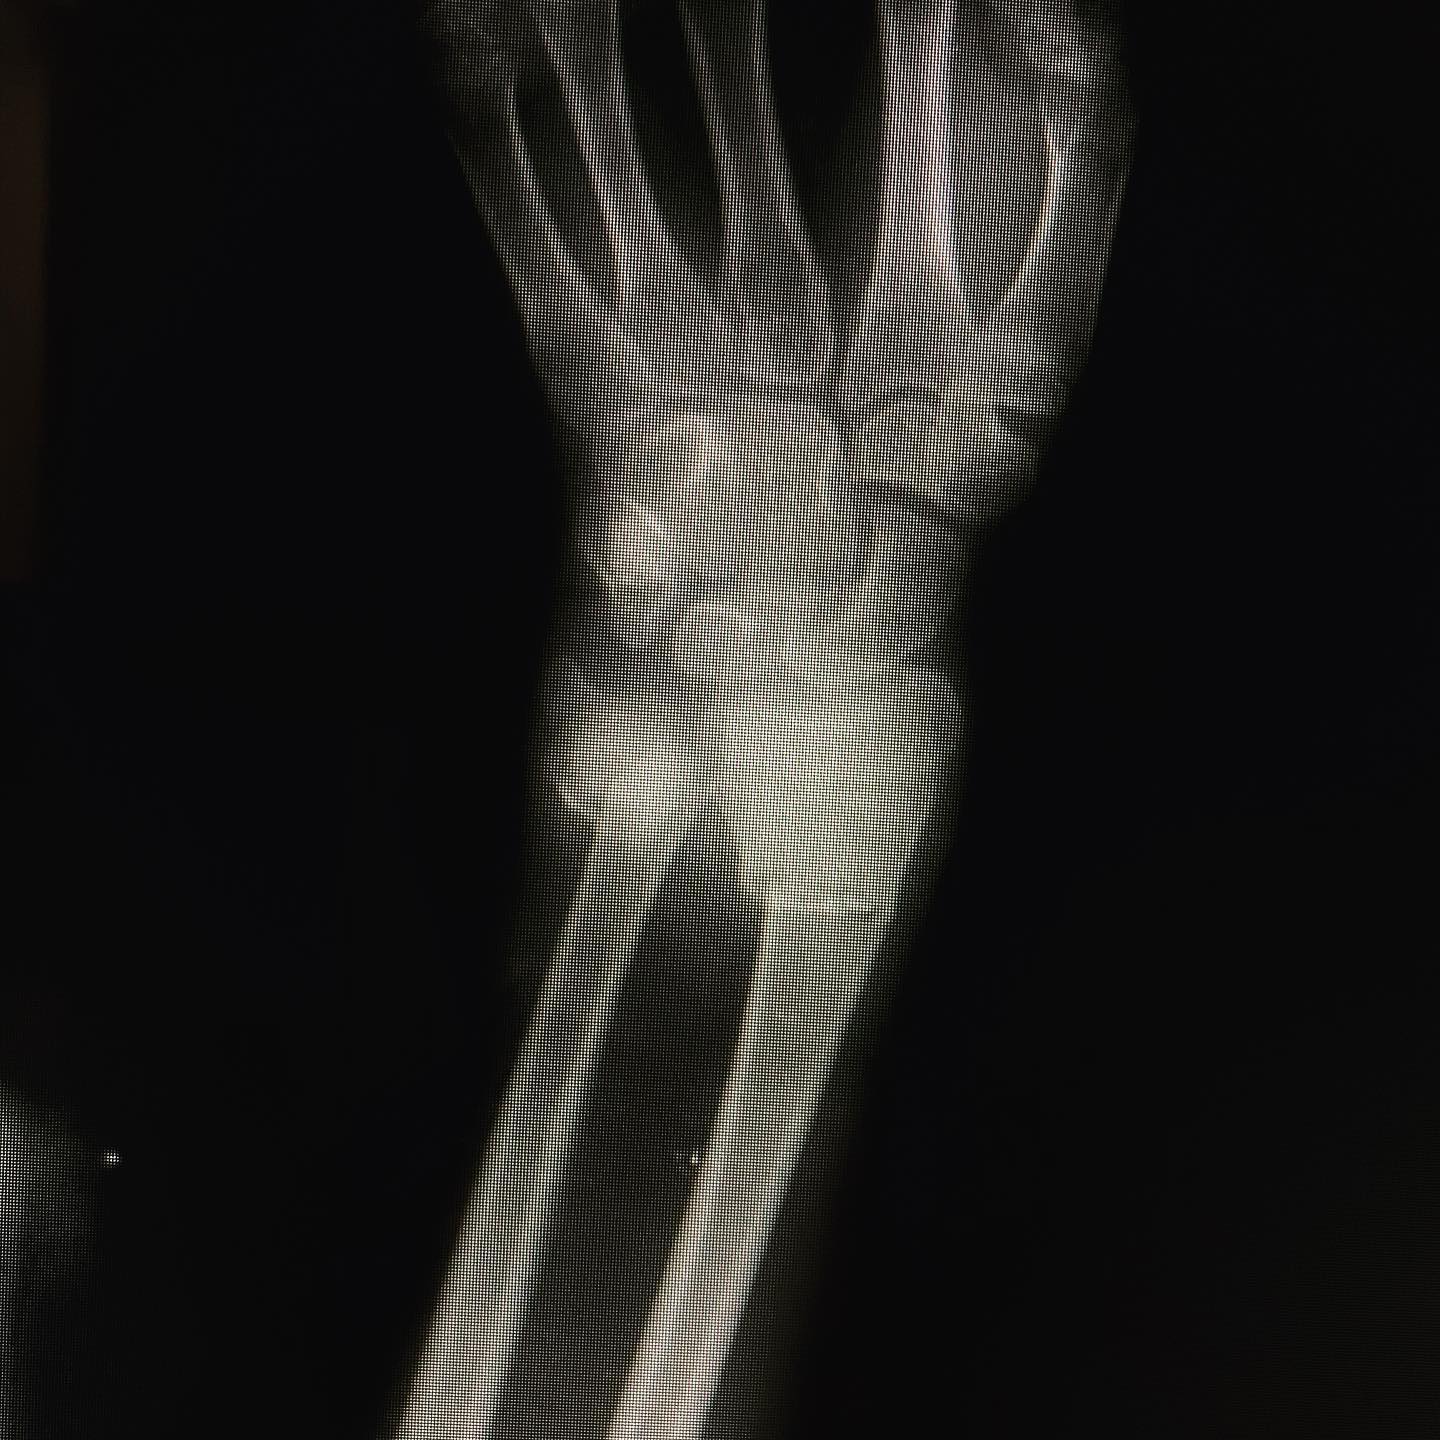

fractura de antebrazo

Cité a Josué para seguimiento y como ya está recuperado al 💯 de la cirugía por fractura de su antebrazo, le di el alta. En su visita me regaló una deliciosa sandía.🍉